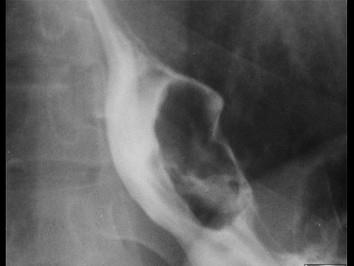

问题 女,32岁,进食后胸骨后疼痛及间歇吞咽困难2年,食管吞钡如图所示,最可能的诊断是 ( )

选项 A、腐蚀性食管灼伤 B、食管裂孔疝 C、贲门失弛缓症 D、食管癌 E、食管平滑肌瘤

答案 E